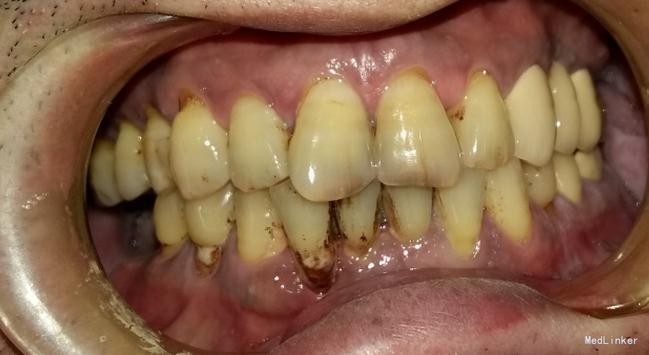

患者,男,45岁,右侧下颌侧切牙严重龋坏,拔除后要求种植修复,平素体质一般,无药物、食物过敏史,无高血压、心脏病等系统病史

种植修复

效果很好,患者满意